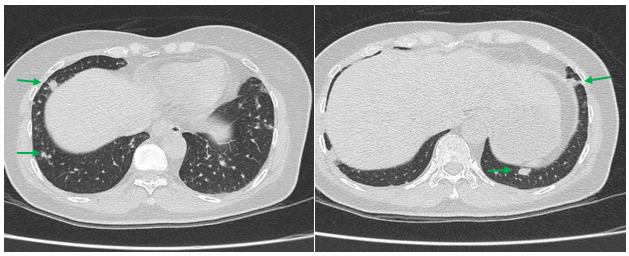

– Chụp cắt lớp vi tính lồng ngực: Nhu mô thùy trên phổi (Phải) có nốt tổn thương kích thước 13x14mm, bờ không đều, ngấm thuốc, sau tiêm. Rải rác nốt đặc 2 bên thùy phổi kích thước 3-10mm. Trung thất các nhóm 1R; 2R; 4R; 5; 8; 10RL có vài hạch lớn nhất kích thước 26x15mm; bờ không đều; ngấm thuốc không đồng nhất sau tiêm. Thượng đòn 2 bên có vài hạch tính chất tương tự; hạch bên phải kích thước 11x14mm

Hình 1. Hình ảnh cắt lớp vi tính ngực có tiêm: thùy trên phổi (P) có nốt tổn thương kích thước 13x14mm, bờ không đều, ngấm thuốc, sau tiêm. Nghi ngờ tổn thương nguyên phát (mũi tên đỏ)

Hình 2: Hình ảnh cắt lớp vi tính ngực có tiêm: Rải rác nốt đặc 2 bên thùy phổi kích thước 3-10mm (các mũi tên màu xanh lá)